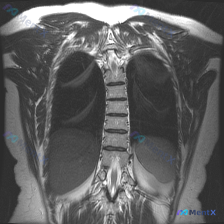

整理到一个很有意思的影像读片材料: 一张胸部MRI-T2序列冠状位影像,原始的影像学分析写的是“胸廓、脊柱、纵隔及肺野解剖结构基本正常,未见明显的病理性高信号改变”,甚至明确提了“椎体信号均匀,骨皮质轮廓清晰,未见明显骨质破坏”。 但拿到这份材料的人,第一眼观察到的线索是——脊柱侧弯(Scolios...

整理到一个挺有意思的病例复盘点,想跟大家讨论下临床思维: - 核心场景:患者主诉“脊柱侧弯”,但拿到的一张胸部冠状位T2 MRI报告里写着「胸椎序列排列整齐,左右基本对称,未见明显异常」。 - 影像背景:图像清晰度良好,胸廓、肺野、上腹部显露部分确实没看到积液、肿块或骨髓水肿信号。 问题来了:这种主...

整理到一份胸椎MRI冠状位T2加权的影像资料,先把核心阳性发现和阴性排查点列出来,大家看看思路会怎么走。 核心阳性表现: - 胸椎整体存在轻度侧向弯曲,左右不对称 关键阴性排查(目前MRI层面): - 脊髓信号正常,连续性好,无受压、增粗或中央管扩张 - 各椎体形态规则,骨髓信号均匀,未见压缩骨折、...